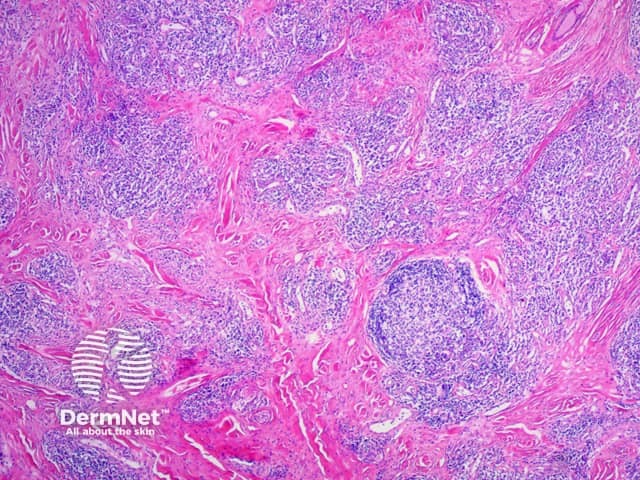

Figure 1

Yokura et al (2014) proposed a classification of IgG4-related skin disease which divides it into primary, mass-forming lesions due to the direct infiltration of plasma cells and secondary lesions which are due to IgG4-mediated inflammation through secondary mechanisms.

The diagnostic criteria on histology proposed for skin disease are the following: